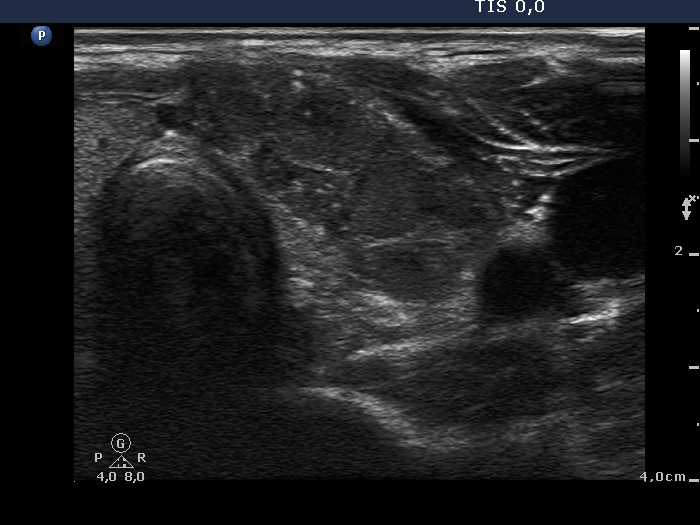

First examination (1st to third rows of images):

Ultrasonography revealed a hypoechogenic nodule in the ventromedial part of the left lobe. The nodule had irregular borders, contained microcalcifications and displayed perinodular and irregular intranodular blood flow.

Histopathology disclosed an embryonal-type follicular adenoma in the left lobe. Almost the entire lobe was consisted of the adenoma. There were within the nodule large fields of lymphocytic infiltration. In the middle portion of the nodule a papillary carcinoma was found with a maximal diameter of 15 mm with metastasis to 3 of the removed 9 lymph nodes in the left side of the neck.

Comments.

It is evident that the cytological material was gained not from the papillary carcinoma but from the adenoma.

It is hard to decide which portion of the lesion corresponded to the carcinoma